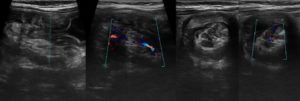

УЗИ через прямую кишку показывает другие срезы, поэтому результаты такой процедуры выглядят иначе:

| Количество слоев стенки | 5 |

| Гиперэхогенность | 1, 3, 5 слои |

| Гипоэхогенность | 2, 4 слои |

| Внутренние контуры стенок | Ровные |

| Внешние контуры стенок | Ровные |

| Регионарные лимфоузлы | Параректальные, до 5 мм |